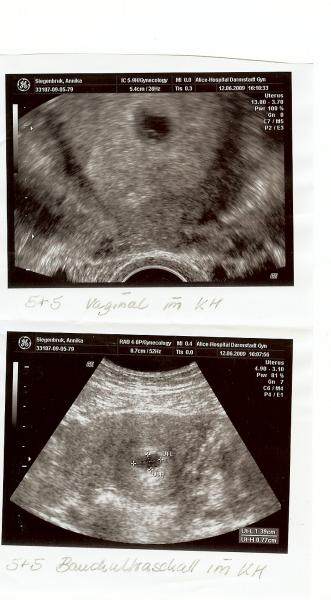

9. ach ja... und ich will ja auch gar keine schlechte Stimmung machen @sabbel ja ich hatte einen Not KS

16. Hallo Mädels, ich wollte Euch nurmal kurz zeigen wie Euer Daumen Drücken geholfen hat:D

18. Am Montag, ich denke mal dann wird man wohl sehen ob alles gut ist, ich bin dann 7+1 da müsste man das Herz und den Knirps richtig sehen, oder? Aber mal ehrlich das bild ist echt wunderschön:D